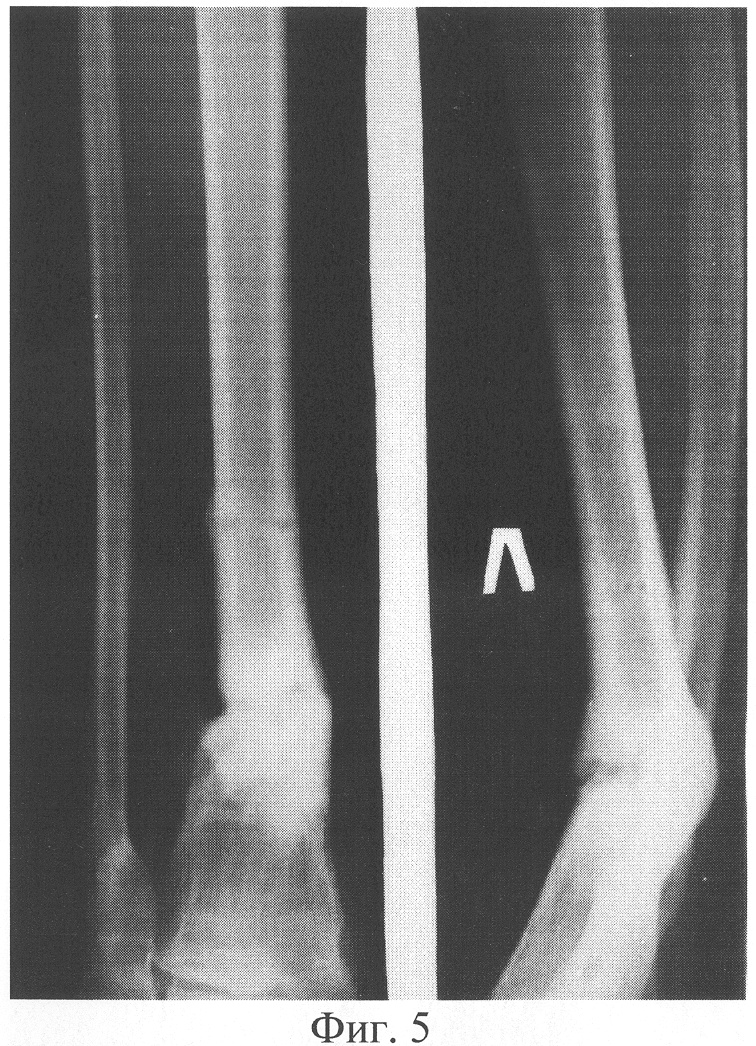

Пример 3. Больной Т., 19 лет, поступил через 745 дней с момента травмы с диагнозом «Посттравматический псевдоартроз нижней трети левой большеберцовой кости. Вальгусно-антекурвационная деформация нижней трети левой голени». Из анамнеза известно, что через 5 дней с момента получения травмы была произведена операция – остеосинтез нижней трети левой большеберцовой кости аппаратом Илизарова. В ходе лечения отмечались следующие жалобы: боли в левой нижней конечности, ограничение функции, возможность передвижения только с двумя дополнительньми опорами. Больной в течение 740 дней лечился с помощью вышеуказанного аппарата, при этом консолидации перелома не наступило. В амбулаторных условиях аппарат внешней фиксации был демонтирован. В результате Т. обратился в клинику травматологии и ортопедии. При проведении клинико-рентгенологического исследования был диагностирован посттравматический псевдоартроз нижней трети левой большеберцовой кости, вальгусно-антекурвационная деформация нижней трети левой голени. Рентгенограмма представлена на фигуре 5. Через 3 дня с момента поступления больному была произведена операция – остеосинтез левой голени аппаратом внешней фиксации спице-стержневого типа, остеотомия левой малоберцовой кости, кортикотомия костей левой голени в нижней трети. Деформация была устранена. После чего в асептичных условиях стерильным скальпелем в стерильном почкообразном лотке измельчили 5 пластин биоматериала аллоплант для склеропластики до размеров крошки 1×1 мм. В условиях операционной у больного осуществили забор крови из кубитальной вены в объеме 5 мл. Затем аутокровь в объеме 5 мл в асептичных условиях перелили в предварительно стерилизованный флакон, куда добавили измельченный биоматериал аллоплант для склеропластики. Место будущей инъекции обезболили 5 мл 0,5% раствора новокаина. Вышеназванные субстанции перемешали и набрали в одноразовый шприц для инъекций, снабженный иглой Гордеева с диаметром отверстия 2 мм, после чего произвели однократную инъекцию лекарственной взвеси в полном объеме в зону ложного сустава. Послеоперационный период протекал без осложнений. Консолидация достигнута через 90 дней (нормальные сроки сращения составляют 75-120 дней, в условиях отягощенного анамнеза – например, при ложном суставе, – затягиваются на неопределенный срок), что подтверждено клинически и рентгенологически. Рентгенограмма представлена на фигуре 6. Осложнений в процессе лечения не было. Получен хороший анатомо-функциональный результат лечения.